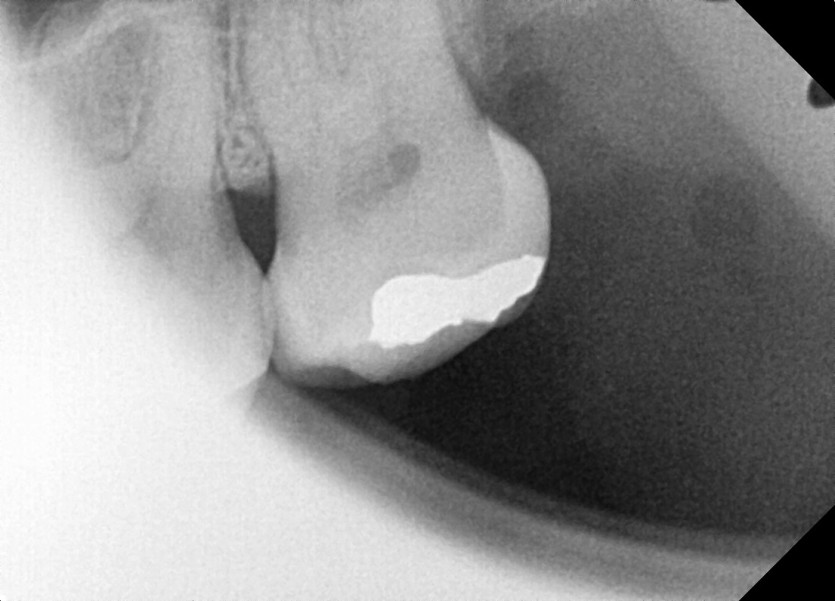

#28 사랑니 발치

구강 외과 전문의가 당일 발치했습니다.